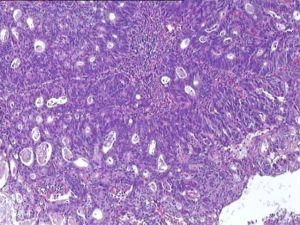

腸鏡檢查可以在直視下肉眼作出診斷,而且可以鉗取腫塊組織作病理切片檢查,以確定腫塊性質及其分化程度,活檢組織行病理檢查是確診直腸癌最好的方法。